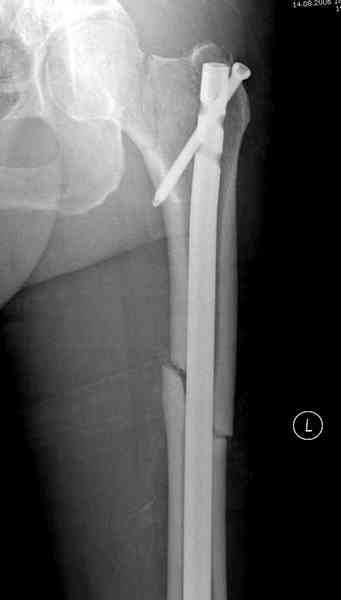

На второй день (7) обнаружен пропущенный перелом,

и проведены шурурпы через и спереди штифта без удаления.

Послеоперационные снимки

Ответные поздравления и пожелания специалистам первой линии обороны! Фиксация вертикального перелома чресшеечными винтами не гарантирует стабильности на период сращения. Будут определенные трудности в определении допустимого режима нагрузки в послеоперационном периоде. С большой вероятностью исход - coxa vara/несращение и дефект кости из-за миграции винтов + ротационная подвижность диафиза на штифте. Напрашивается более биомеханически обоснованный реостеосинтез после выведения больного "из состояния".